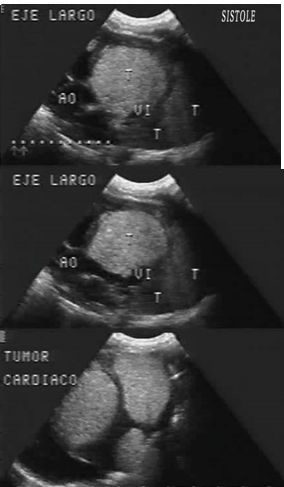

El estudio Ecocardiográfico demostró la presencia de múltiples tumoraciones cardíacas, presentando dos de ellas de gran tamaño una se localizaba en el tabique interventricular 36 x 28 mm y la otra ocupaba la pared posterior del ventrículo izquierdo 34 x 25 mm las cuales producían una restricción del ventrículo izquierdo y una obstrucción ligera del tracto de salida de dicho ventrículo, presentando un gradiente a nivel del tracto de salida del ventrículo izquierdo de 50 mmHg.

Figura # 3: Zonas hiperecogénicas en tabique interventricular y pared posterior de ventrículo izquierdo. Estrechez del Tracto de salida del ventrículo izquierdo.